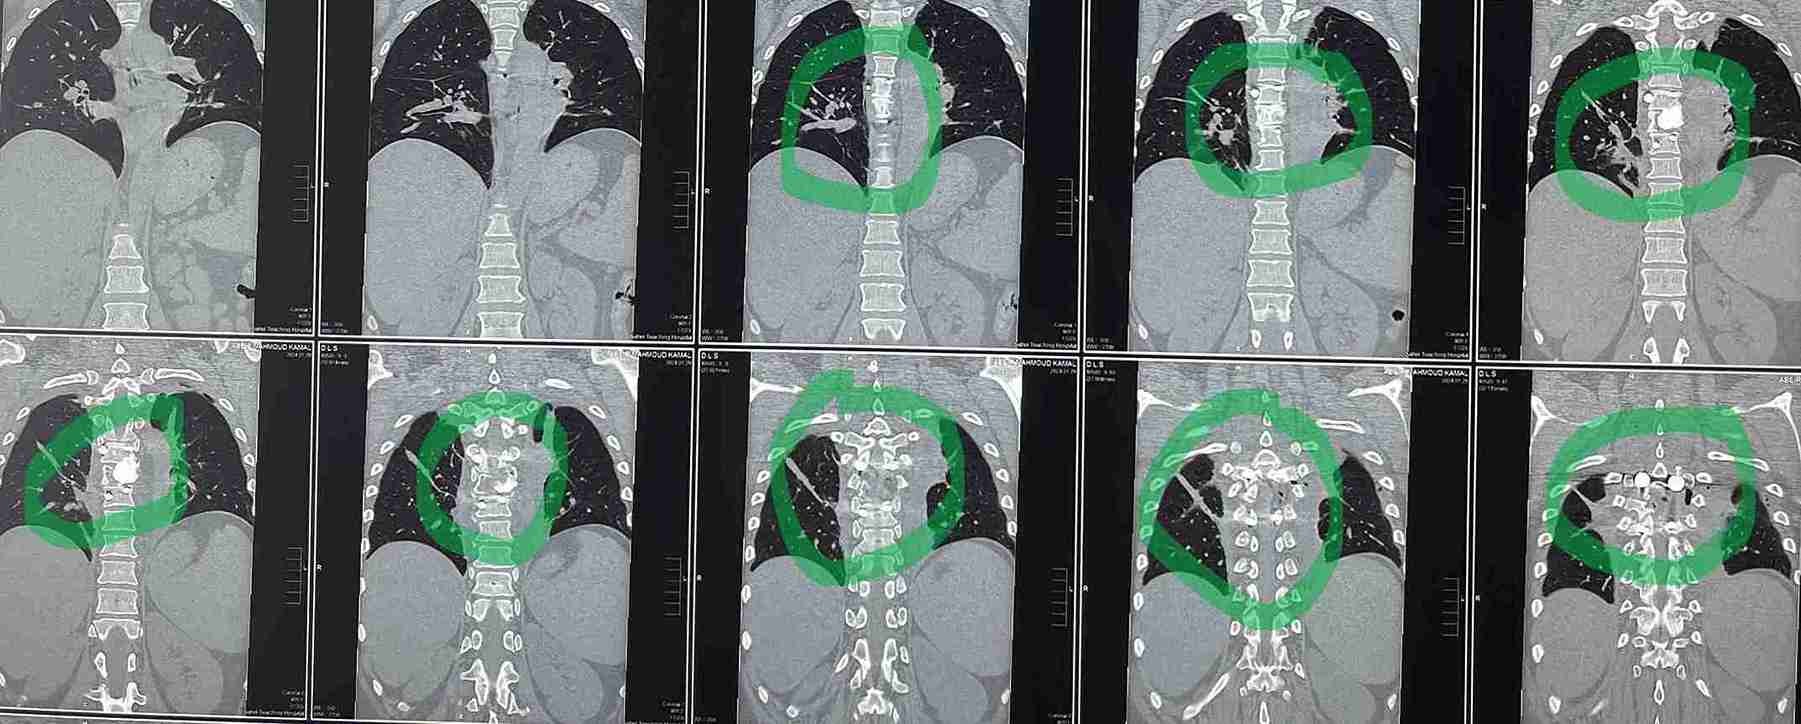

مريضة عمرها 43 عام تعاني من ضعف متزايد بالطرفين السفليين.

43-year-old female patient suffers from increasing weakness in the lower extremities

A 43-year-old woman suffering from progressive weakness in both lower limbs was diagnosed and treated. This condition affects walking ability and mobility, requiring thorough neurological evaluation to determine the underlying cause and develop an appropriate treatment plan.

• Accurate diagnosis using latest neuroimaging techniques